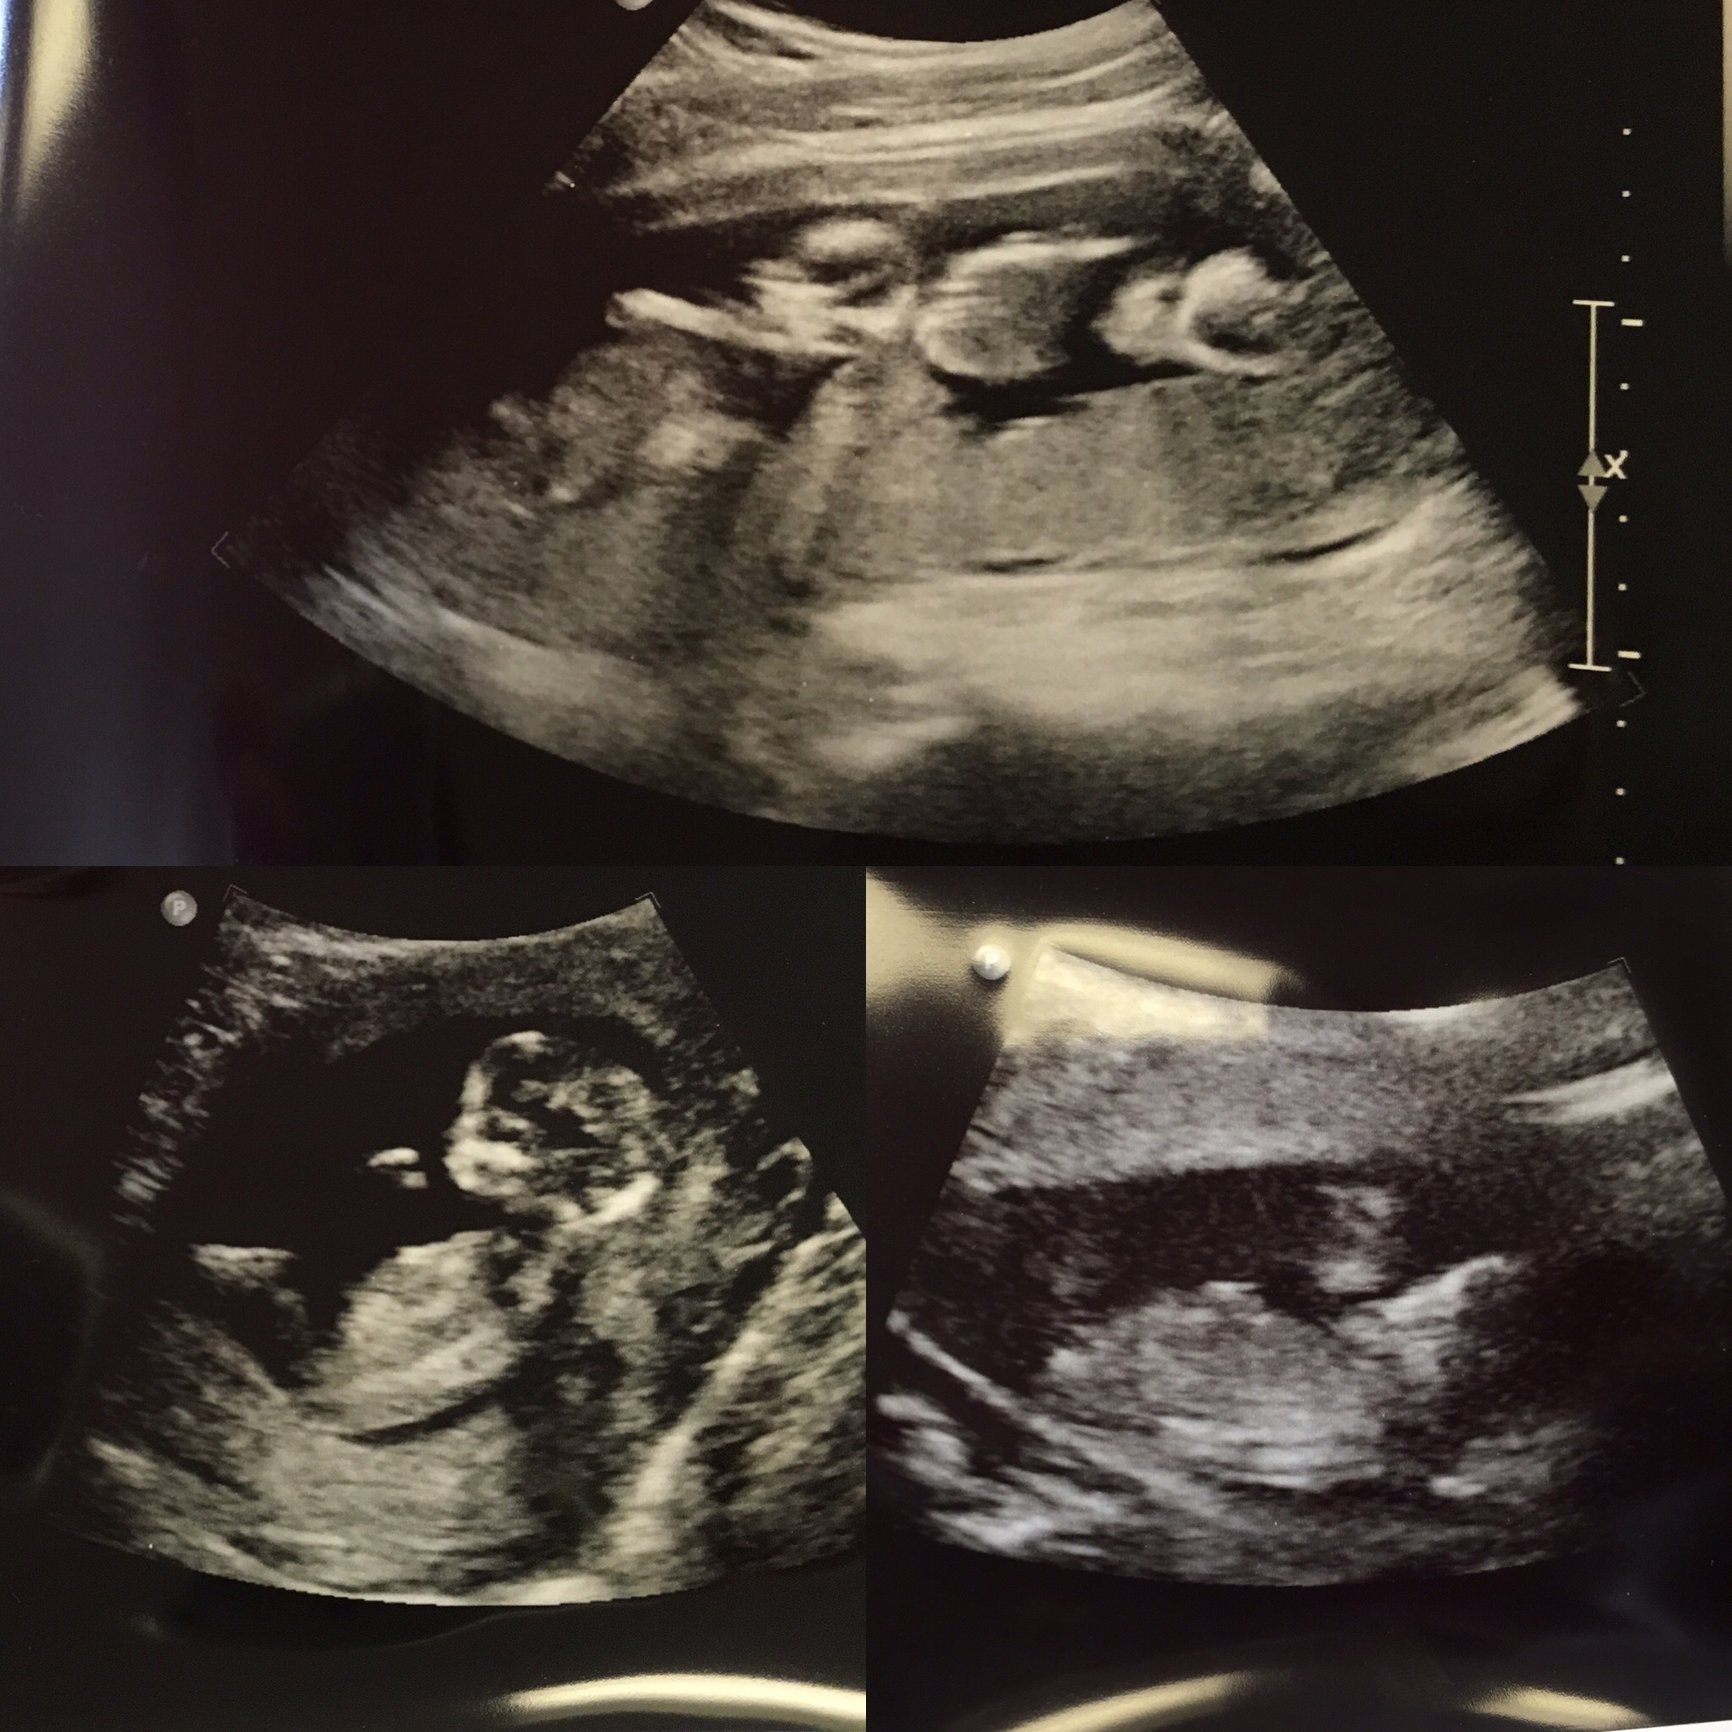

Had my second appointment and ultrasound today! Both doing amazing. We got to see them moving around, and hear their heartbeats! My doctor says I will have an ultrasound each time I come in, because it's the only way they can truly differentiate between the heartbeats.

@brittnic86 cute pics- really looking like babies! I'm a little worried to get so many ultrasounds.... though I know there isnt really a way around it...